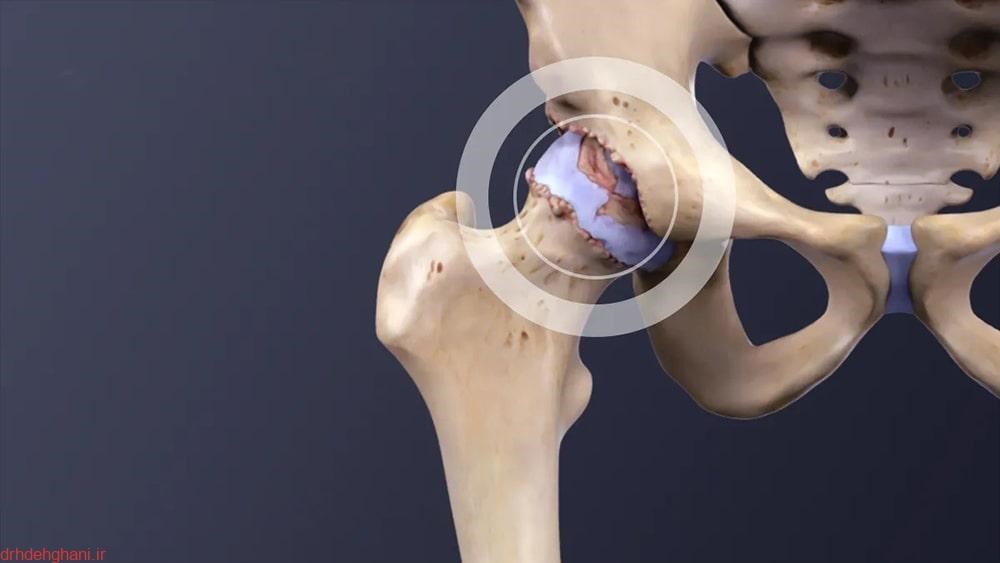

به زبان ساده، آرتروز لگن به حالتی گفته می‌شود که در آن غضروف مفصل لگن، که نقش محافظ و ضربه‌گیر بین استخوان‌ها را دارد، به مرور زمان دچار ساییدگی و فرسایش می‌شود. در نتیجه، استخوان‌ها روی هم سایش پیدا می‌کنند و این موضوع باعث درد، خشکی و محدودیت حرکت می‌گردد. شاید تصور کنید این مشکل فقط برای سالمندان پیش می‌آید، اما واقعیت این است که آرتروز لگن می‌تواند در هر سنی بروز کند؛ از ورزشکارانی که فشار زیادی به مفاصل وارد می‌کنند تا افرادی که به دلیل اضافه‌وزن یا سابقه آسیب‌دیدگی لگن در معرض خطر هستند.

• سابقه آسیب‌دیدگی یا جراحی: شکستگی لگن، دررفتگی یا جراحی‌های قبلی می‌تواند باعث تغییر شکل مفصل و شروع آرتروز شود.